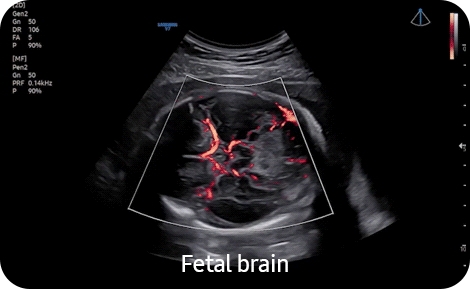

• 5D CNS+- Модуль автоматического получения 9 стандартных поскостей головного мозга плода и последующих автоматических измерений стандартных параметров фетометии головного мозга плода 5D CNS из объемных данных. Необходим модуль 4D. (CV1-8AD);

• Высокочувствительный направленный энергетический допплер S-Flow позволяет визуализировать даже самые мелкие сосуды

• MV-Flow- Инновационный режим для картирования капиллярного и низкоскоростного кровотока MV-Flow. Подходит для наблюдения за микроциркуляцией и медленным кровотоком в объемных образованиях (CA1-7SD, CA3-10A, LA2-14A, LA4-18AD, LA3-22AI, EA2-11ARD/AVD,miniER7, CV1-8AD, EV2-10A);